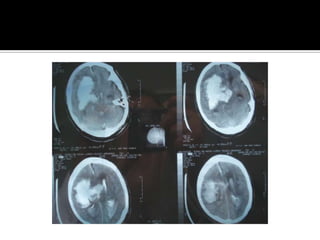

Caso clinico Mujer de 20 años , puérpera, llega a Hospital la catalogan como psicosis postparto. Dos días después coma y , después muerte cerebral. La TAC erróneamente fue interpretada como infartos lacunares.

Caso clinico Mujerde 20 años , puérpera, llega a Hospital la catalogan como psicosis postparto. Dos días después coma y , después muerte cerebral. La TAC erróneamente fue interpretada como infartos lacunares.

Hemorragia cerebral IntraparenquimatosaCefaleaAlteracion de la concienciaVomitoCrisis epilepticasDiagnostico: TAC de craneo simple

Hemorragia cerebral IntraparenquimatosaCefaleaAlteracionde la concienciaVomitoCrisis epilepticasDiagnostico: TAC de craneo simple

Hemorragia cerebral IntraparenquimatosaSitio : putaminal, nucleo caudado , talamo,lobar, cerebelosa y  puente.Etiologia : HTA,malformacion AV, angioma cavernoso y angiopatiaamiloide, drogas ( cocaina,heroína, fenilpropanolamina) anticoagulantes , tromboliticosMas de la mitad de pacientes, muere o queda con secuelas severas

Hemorragia cerebral IntraparenquimatosaSitio: putaminal, nucleo caudado , talamo,lobar, cerebelosa y puente.Etiologia : HTA,malformacion AV, angioma cavernoso y angiopatiaamiloide, drogas ( cocaina,heroína, fenilpropanolamina) anticoagulantes , tromboliticosMas de la mitad de pacientes, muere o queda con secuelas severas